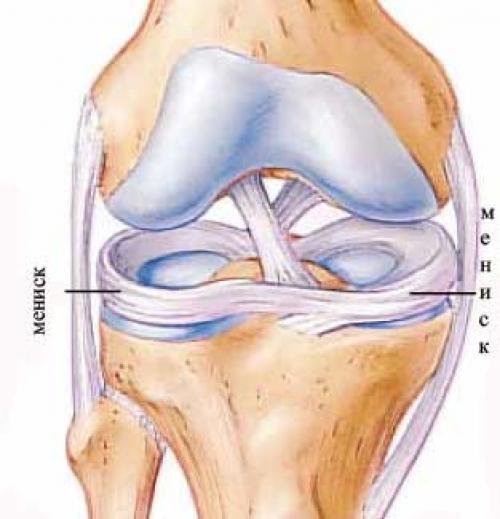

Анатомические изображения менисков и коленного сустава

Раздел: Иллюстрированные советы